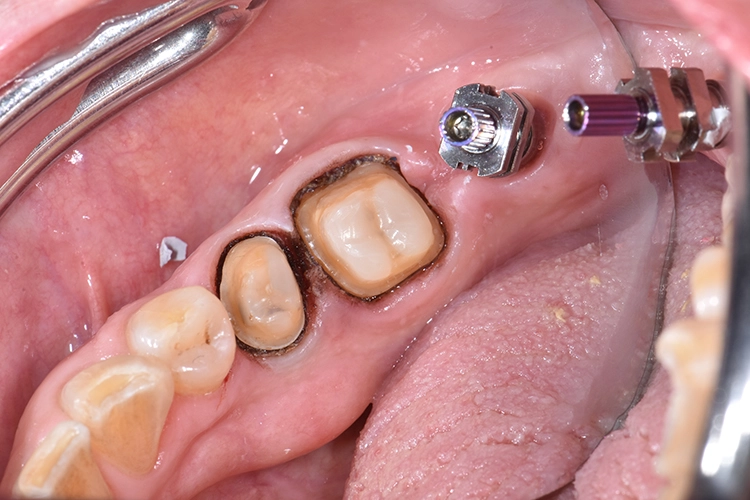

Bilder: Dr. Lampson / HannkerHierzu wurde der Gingivaformer entfernt und ein Abformpfosten auf Implantatniveau inseriert. Retraktionsfäden an den Pfeilerzähnen 45 und 46 dienten dazu, die Präparationsgrenze aufzuzeigen (Abb. 6). Anschließend kam ein Guttapercha-Druckverband zum Einsatz, um die marginale Gingiva zusätzlich zu verdrängen (Abb. 7).

Dieser wurde erst unmittelbar vor der Applikation des Abformmaterials entfernt. Für die Abformung an sich, fiel die Wahl auf eine einseitige Doppelmischtechnik (Abb. 8). Im nächsten Schritt wurde mit einem dualhärtenden Composite für provisorische Kronen und Brücken (TEMPSMARTTM DC, GC) die vorläufige Versorgung an den Zähnen 45 und 46 angefertigt (Abb. 9 und 10a bis c) und mit FREEGENOL (GC) befestigt.